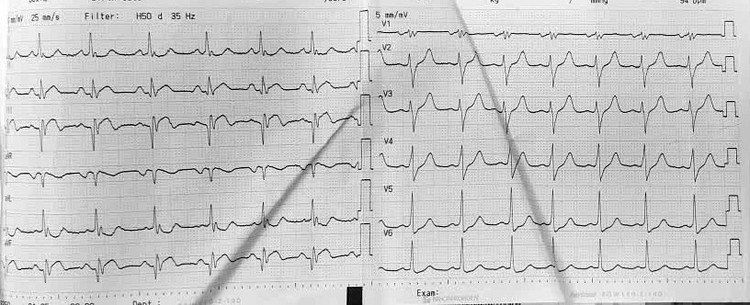

Điện tim bệnh nhân Q. trước mổ bình thường. Ảnh BV